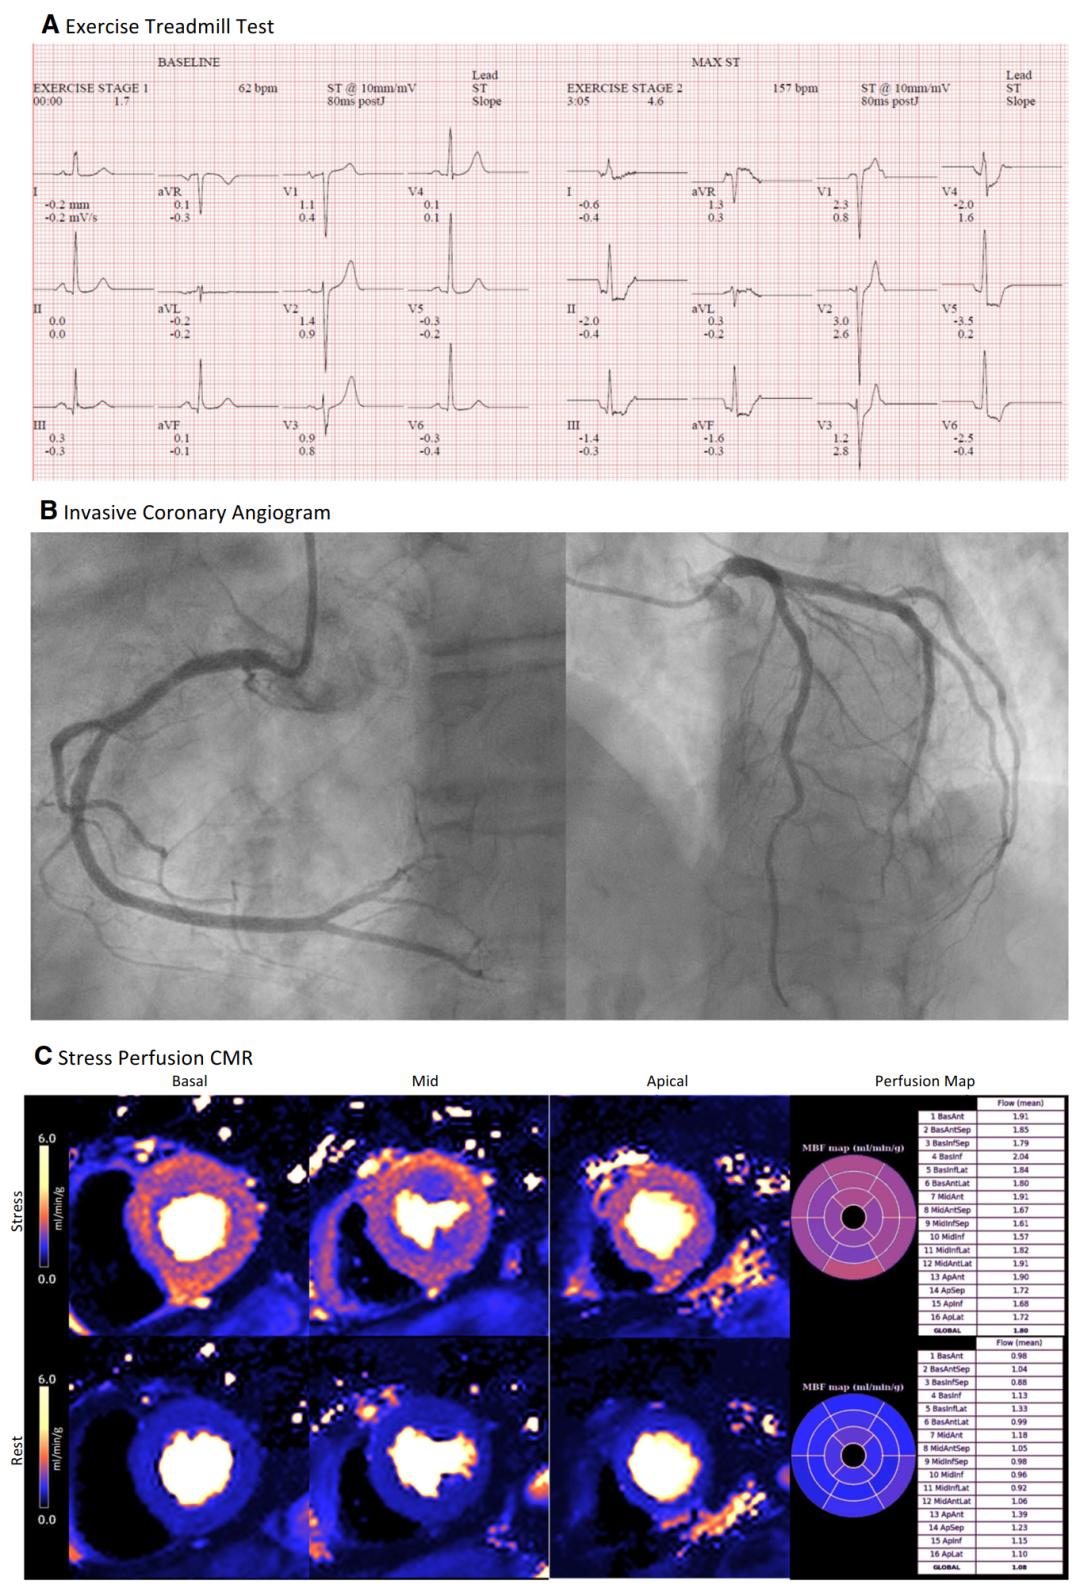

图3 70岁女性,因胸痛而反复住院,性别特异性高敏感性肌钙蛋白I浓度(<16 ng·L)正常,进行多模式检查。A运动心电图试验显示广泛水平ST段压低,缺血呈强阳性。B侵入性冠状动脉造影仅显示轻微动脉粥样硬化斑块,无梗阻性CAD。C负荷/静息灌注CMR成像结合心肌血流的inline像素映射显示周围心内膜下灌注缺损,负荷MBF减低(全局负荷MBF=1.80 mL·min−1·g−1),以及MPR较低(全局MPR=1.67)。这些发现可诊断CMD。最终诊断为微血管性心绞痛。